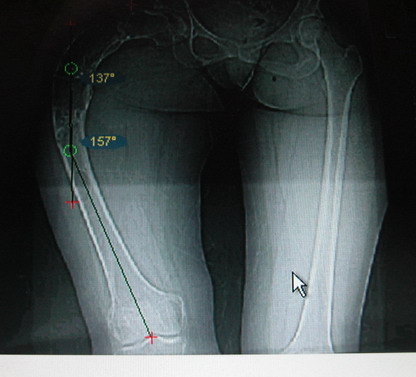

Возможна аппаратная коррекция оси с формированием клиновидного регенерата, которая решила бы и проблему укорочения (что, впрочем, нужно уточнить по схеме, сделанной по рентгенограмме с хорошим захватом смежных суставов - схемка по присланному снимку в приложении). По окончании коррекции - блокируемый стержень, который и сократит время пребывания в аппарате, и вообще возврата к нормальной жизни, а также будет мерой профилактики патологических переломов.

Собственно сустав не беспокоит, объем движений полный. По скиаграммам получается, что достаточно одной остеотомии на вершине деформации, чтобы восстановить длину и вывести коленный сустав в нужное положение.

Моё мнение, что двойная остеотомия бедра с аппаратом Илизарова + Гексаподный механизм, или Тэйлора, В данной ситуации является методом выбора. Я очень извеняюсь за качество прилагаемых снимков, в которых я постарался отразить разницу междe одной и двумя остеотомиями бедра.